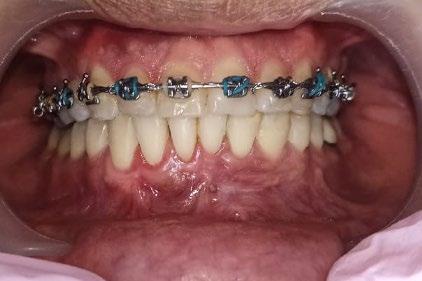

El tratamiento se realizó en las siguientes fases: la fase prequirúrgica incluyó la alineación, nivelación y la

extracción de los segundos premolares superiores e inferiores, con cierre de espacios. En la fase quirúrgica, se realizó una mentoplastia de avance e implantes en la zona malar. La fase postquirúrgica consistió en el detallado-retención. La aparatología utilizada fueron brackets de prescripción Roth .022 × .028; se colocaron bandas en los primeros molares superiores e inferiores, con tubos punteables en los O.D. 16, 26, 36 y 46, y tubos bondeables en el O.D. 27, además de un arco transpalatino y un arco lingual.

El tratamiento se realizó en las siguientes fases: la fase prequirúrgica incluyó la alineación, nivelación y la extracción de los segundos premolares superiores e inferiores, con cierre de espacios.

El tratamiento concluyó en 2 años y 6 meses, logrando el perfil facial deseado, con clase I esquelética, clase I canina y molar bilaterales, corrección del apiñamiento maxilar y mandibular, líneas medias coincidentes, overjet y overbite adecuados, así como la realización de la genioplastia e implantes en la zona malar. En los

En los estudios finales en las fotografías intraorales (Figura 9) se ve la línea media coincidente, el overjet y el overbite. La alineación y forma de las arcadas superior e inferior, con el

retenedor fijo de premolar a premolar (Figura 10).